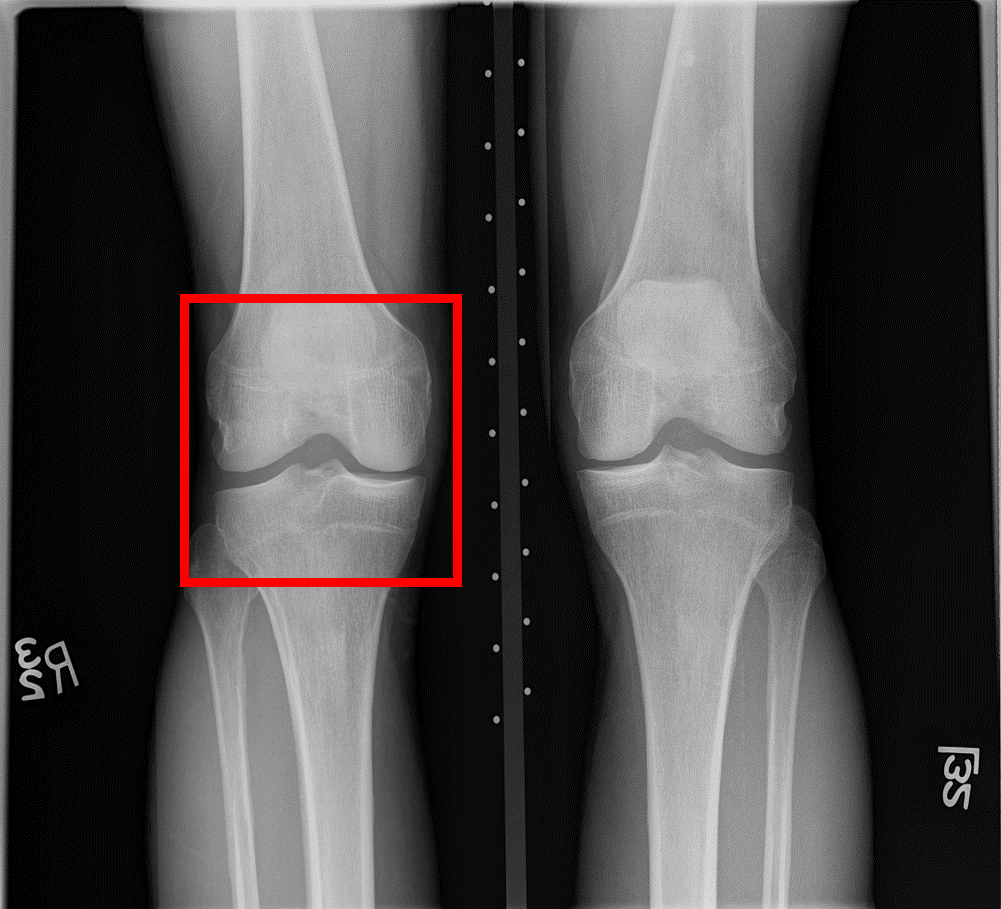

Refer to caption

Figure 6: A knee radiograph from the OAI database with the extracted knee joint in the red box (a). Obtained knee joint (b).

As shown in Fig. 6, as in [32], knee joints were detected using the learning model, YOLOv2 [33] and served as inputs of the proposed model. As a result of the preprocessing steps, 3,185 KL-0 and 2,126 KL-2 images were collected. According to each KL grade, the dataset was randomly divided into training, validation, and test sets with a ratio of 7:1:2, respectively.